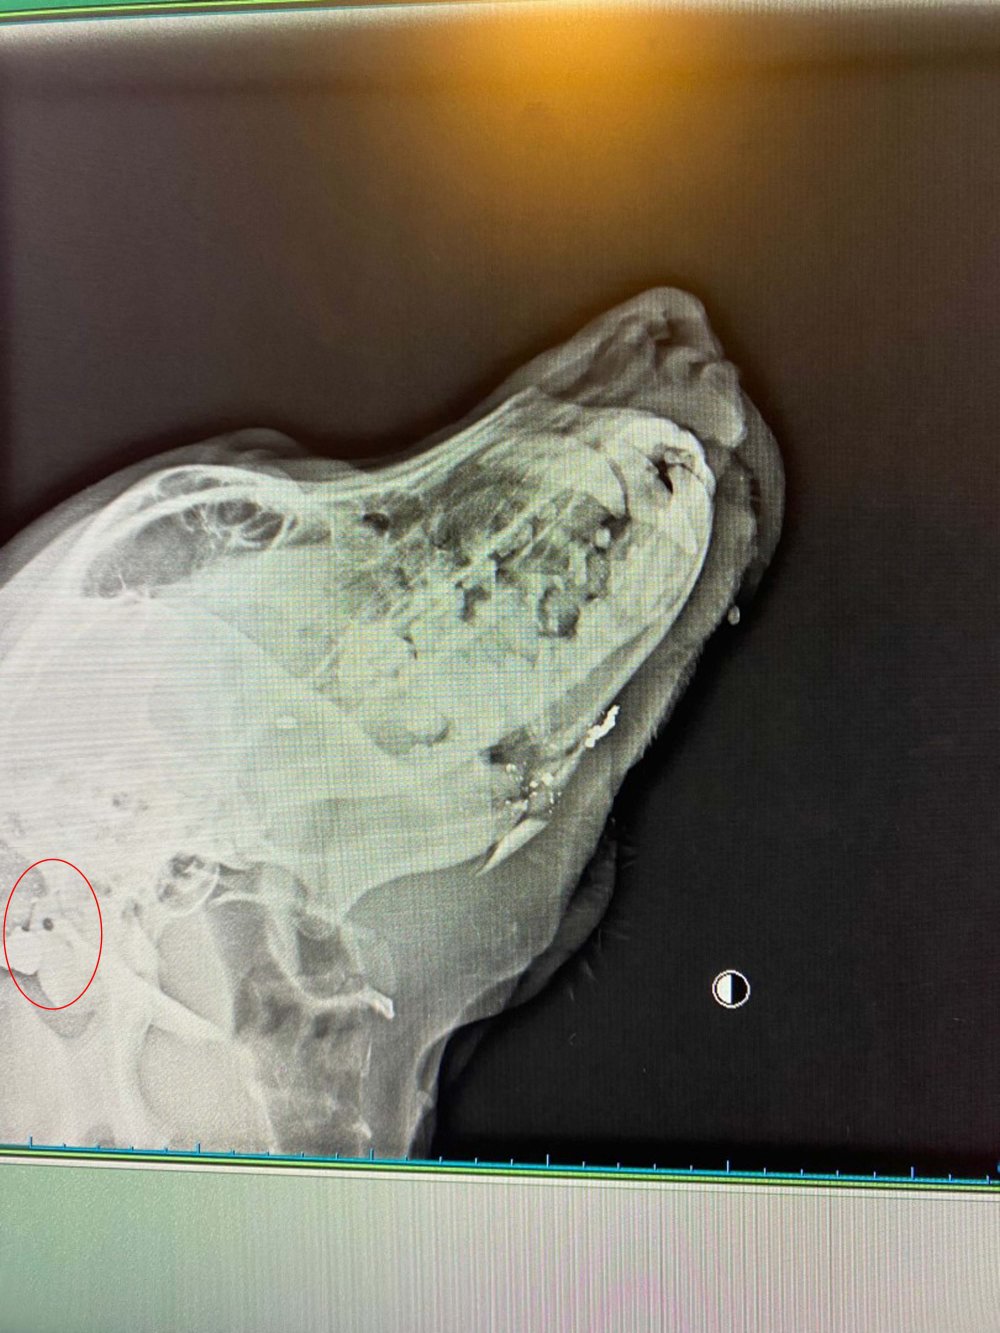

Olay, 11 Ağustos Pazar günü, Milas'a bağlı Meşelik Mahallesinde meydana geldi. Bölgedeki esnaf tarafından bakılan sokak köpeği, kanlar içerisinde bulundu. Yaralı köpek, Bodrum'da bulunan özel bir veteriner kliniğine kaldırıldı. Yapılan tetkiklerde köpeğin tabanca ile açılan ateş sonucu yaralandığı, kurşunun boyun bölgesinden girdiği ve çenesinin dağıldığı tespit edildi. Durumu stabil olan yaralı köpek, ameliyata alınacak. Şikayet üzerine jandarma ekipleri, köpeği kimin vurduğunun belirlenmesi ve yakalanması için çalışma başlattı.